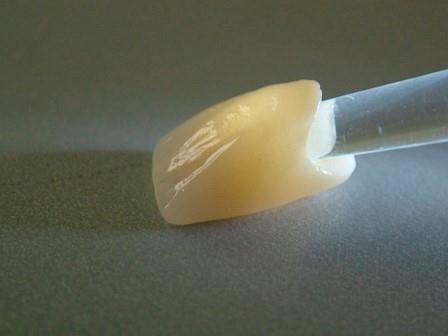

Готовая коронка на каркасе из оксида циркония

Готовая коронка на каркасе из оксида циркония